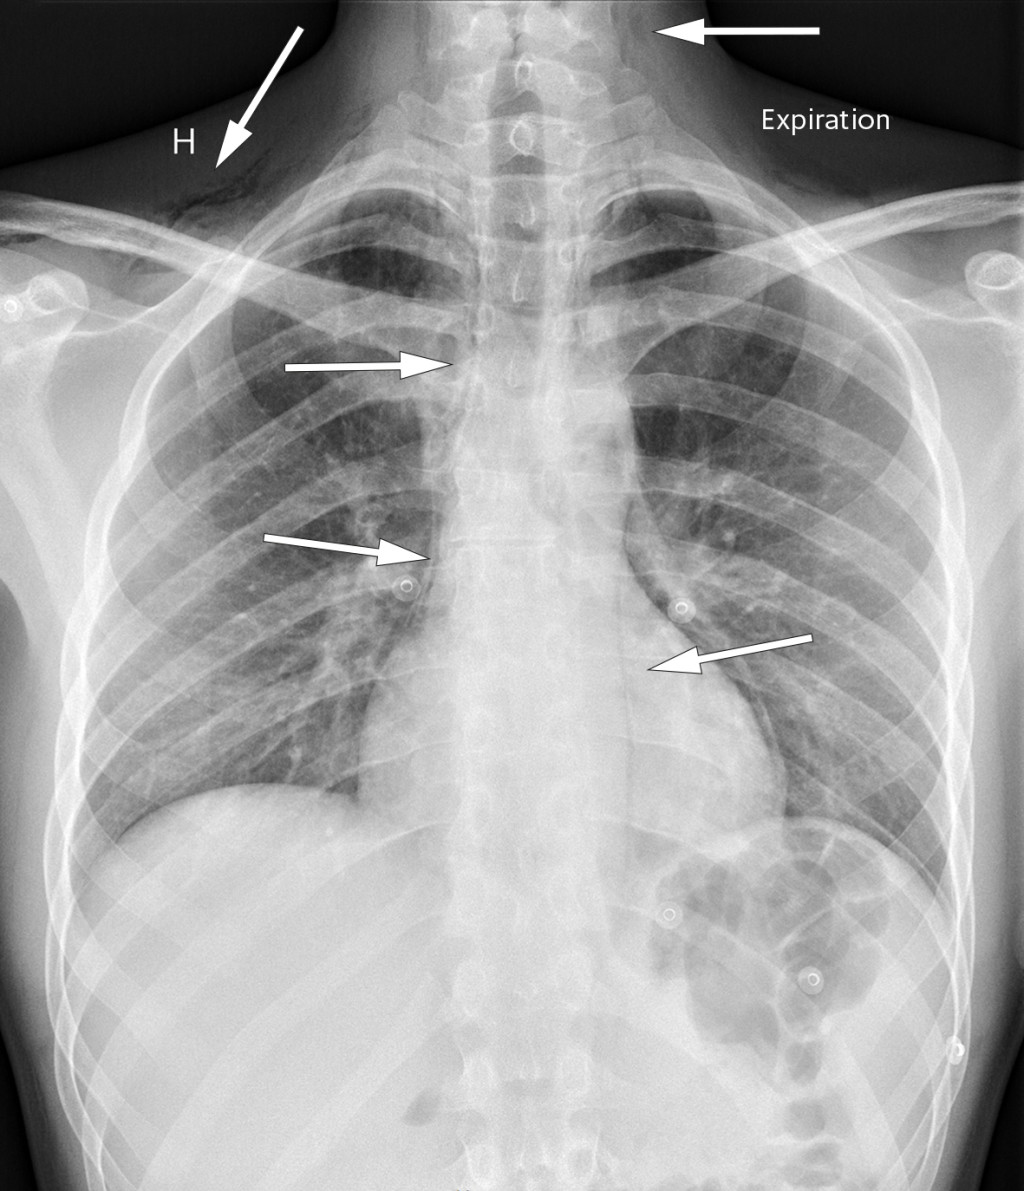

The chest x-ray shown is of a man in his twenties who experienced acute chest pain with accompanying dyspnoea while resting. The pain radiated to both shoulders and to the back, and was exacerbated by inspiration. He had stable vital parameters and blood tests were normal.

The chest x-ray showed air in the soft tissue of the neck and bilaterally in the supraclavicular region, along the trachea, heart, and along the aortic contour laterally. A thoracic CT without intravenous contrast confirmed pneumomediastinum and excluded pneumothorax. At clinical examination three weeks later the patient no longer had symptoms, and chest x-ray showed complete regression of the pneumomediastinum.